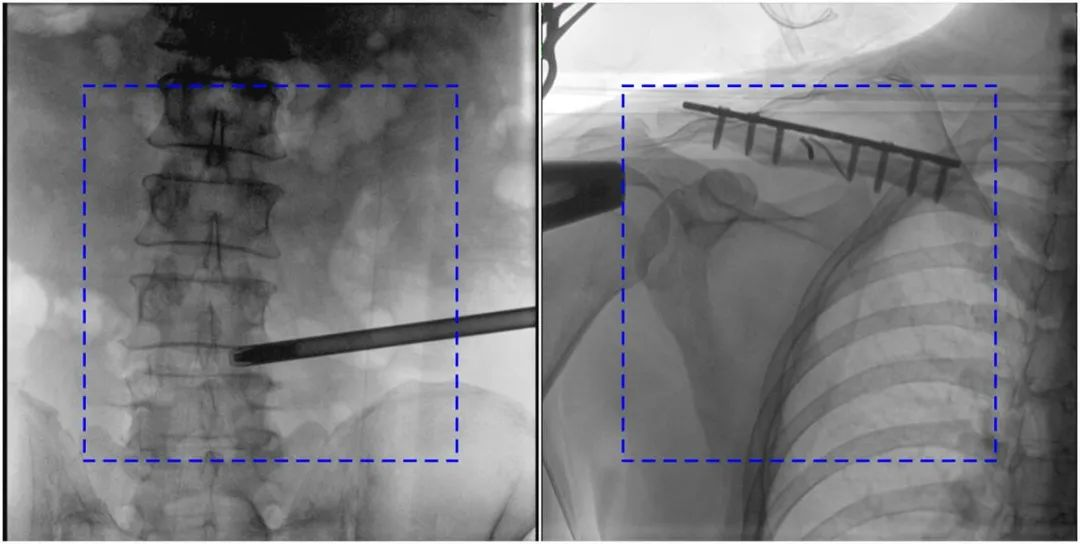

與傳統(tǒng)的21CM×21CM成像尺寸相比,普愛醫(yī)療大平板一體式C形臂具有30CM×30CM更大成像尺寸,能夠一次成像5.5節(jié)椎體,呈現(xiàn)更全面的影像信息,即便是手術(shù)經(jīng)驗不豐富的年輕醫(yī)生也能通過圖像迅速判斷椎體節(jié)段、定位手術(shù)部位,避免因為視野不足而造成的多次定位、反復(fù)曝光,提高效率的同時避免過量攝入輻射。

普愛醫(yī)療大平板一體式C形臂圖像與傳統(tǒng)圖像對比(藍色虛線內(nèi)為傳統(tǒng)21CM×21CM平板的成像區(qū)域)